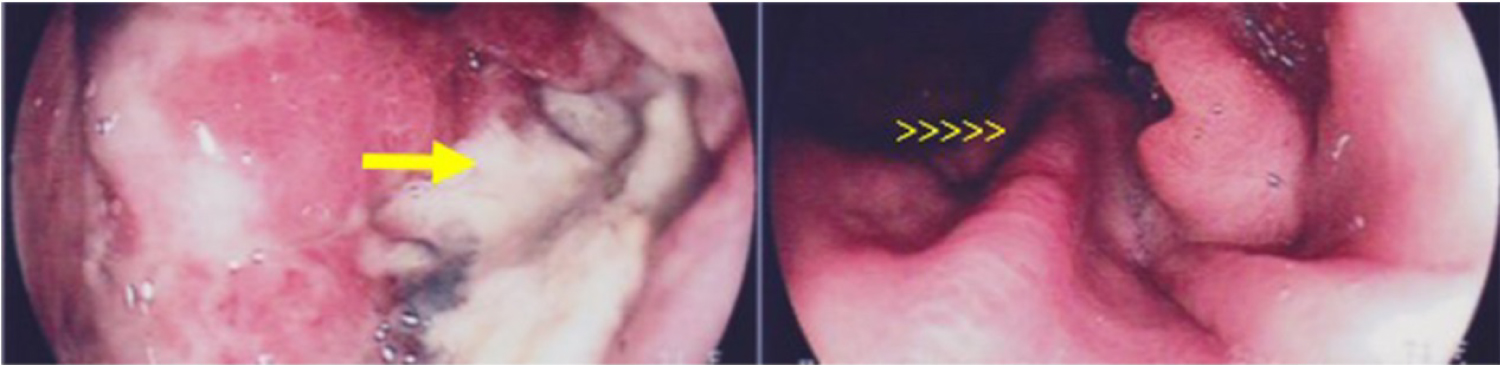

A 72-year-old woman in June 2015 was diagnosed with AJEG G2 (Figure 1 and Figure 2). The oncologist suggested a neoadjuvant chemotherapy scheme with Capecitabine, Oxaliplatin, and Epirubicin (EOX). However, this was not approved because of the cardiotoxicity of Epirubicin since the patient had coronary artery disease and a stent installed. Therefore, neoadjuvant chemotherapy was administered with only Capecitabine plus Oxaliplatin. Unfortunately, she had a severe infusion reaction with edema of the glottis during the second application of Oxaliplatin, preventing its further use. This was then followed by therapy with Capecitabine alone, because of which the patient developed extensive gastrointestinal toxicity requiring prolonged hospitalization, experienced significant weight loss (20 kg in 33 days) and underwent a gastrostomy. We chose to stop the neoadjuvant chemotherapy, and during the months of recovery, she had progression of local disease. In November 2015, the patient underwent gastroesophagectomy (total esophagectomy with extensive gastrectomy and creation of a neoesophagus with great gastric curvature) with an uneventful postoperative period. She had six months without any cancer treatment. In May 2016, a positron-emission tomography and computed tomography (PET-CT) performed on the patient identified nodal, liver, and peritoneal progression and prompted an examination with Personna® Onco, a genetic analysis tool that uses sequencing technology for analysis of multigenic next-generation sequencing (NGS). This examination discarded HER-2 changes and identified the PI3Kca mutation.

Figure 1: Upper Gastrointestinal Endoscopy showing deep ulceration in the gastric esophagus transition (arrow) and in rear view shows the folds (arrowheads). View Figure 1